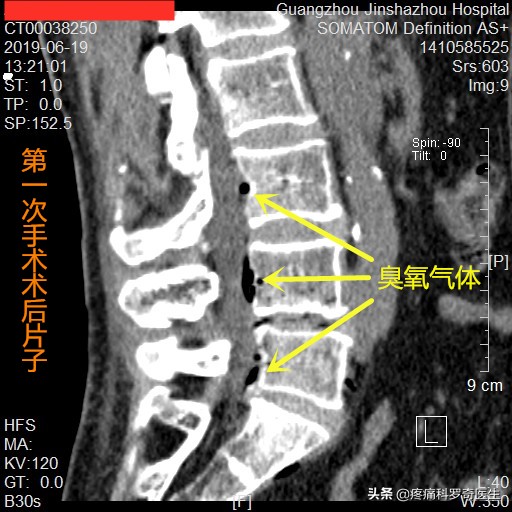

第一次住院,术后臭氧气体扩散情况

第一次手术,我们可以看到椎管内的臭氧气体(箭头所指),在椎管内只扩散了2~3个节段,说明,椎管内存在着大面积的粘连,整个手术完成后,患者缓解了一半的症状。